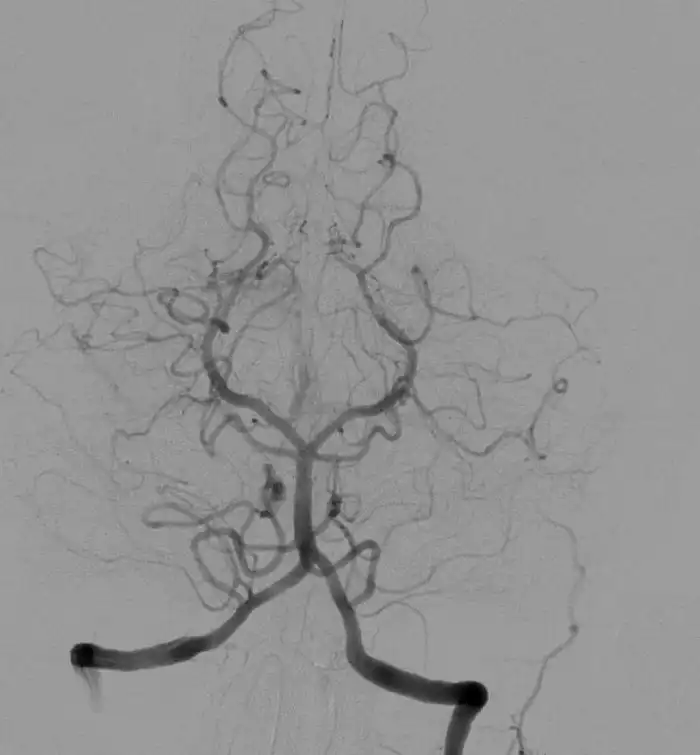

Затем придумали добавлять контрастные материалы. Помните про неоднородность снимков? В вас, например, можно залить сульфат бария, перорально или нецензурно, и пофотографировать в Икс лучах в разных позах. Или, что ещё технологичнее, запустить в КТ и получить 3д модель вашего кишечника, потому что на рентгене вы будете просвечивать, а барий - нет. Он заполнит вас изнутри прохладной склизкой массой и покажет опытному диагносту все ваши складочки. Можно ввести контрастное вещество в сосуды, и здесь вам придется ещё тяжелее. Компьютерная томография с подсветкой сосудов (то бишь ангиограмма) в среднем даст вам 16 мЗв, а максимально 32 мЗв.